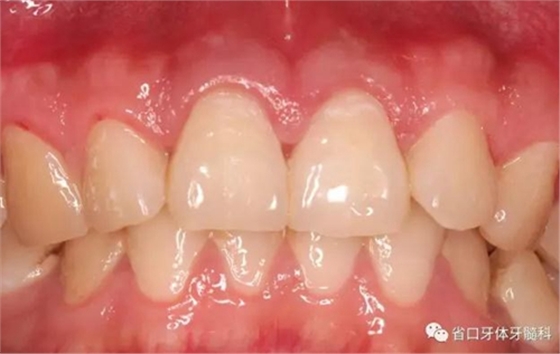

圖1:術(shù)前口內(nèi)照

檢查:11、21牙體組織完整,冷熱刺激無明顯疼痛不適,叩診+,松-,牙齦無紅腫,探診深度2-3mm,電活力測試同正常對照牙,數(shù)值為5,正常對照牙為4;